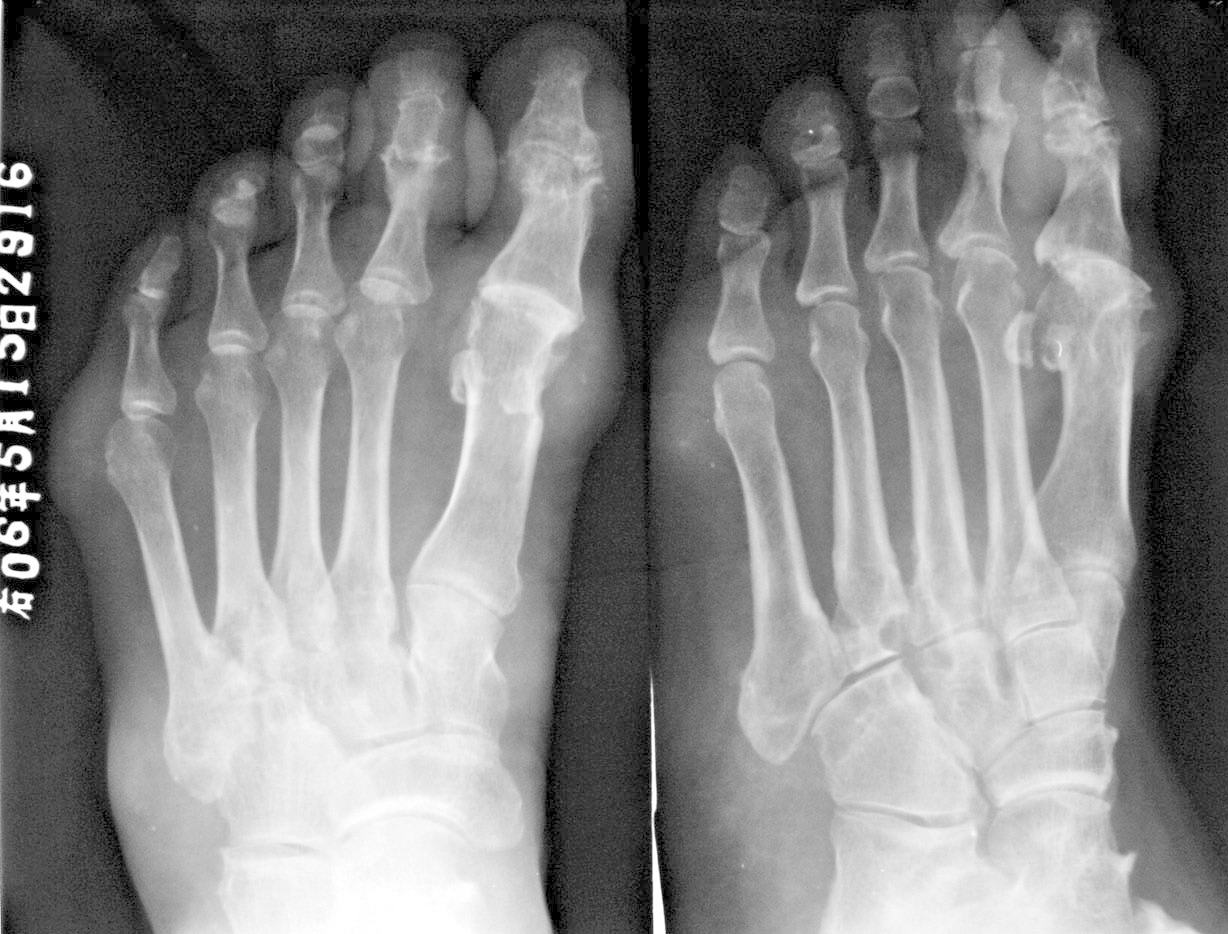

不用病史大家一看就知道是什么了!

痛风。

痛风 典型

痛风.并且可见到痛风石

支持痛风---穿凿状破坏,软组织肿块,痛风石形成。

穿凿样骨质破坏及及足、外踝痛风结节形成符合痛风性关节炎。

尿酸高,该患者患病已经近十年,双手及双足均可见多发明显病变。